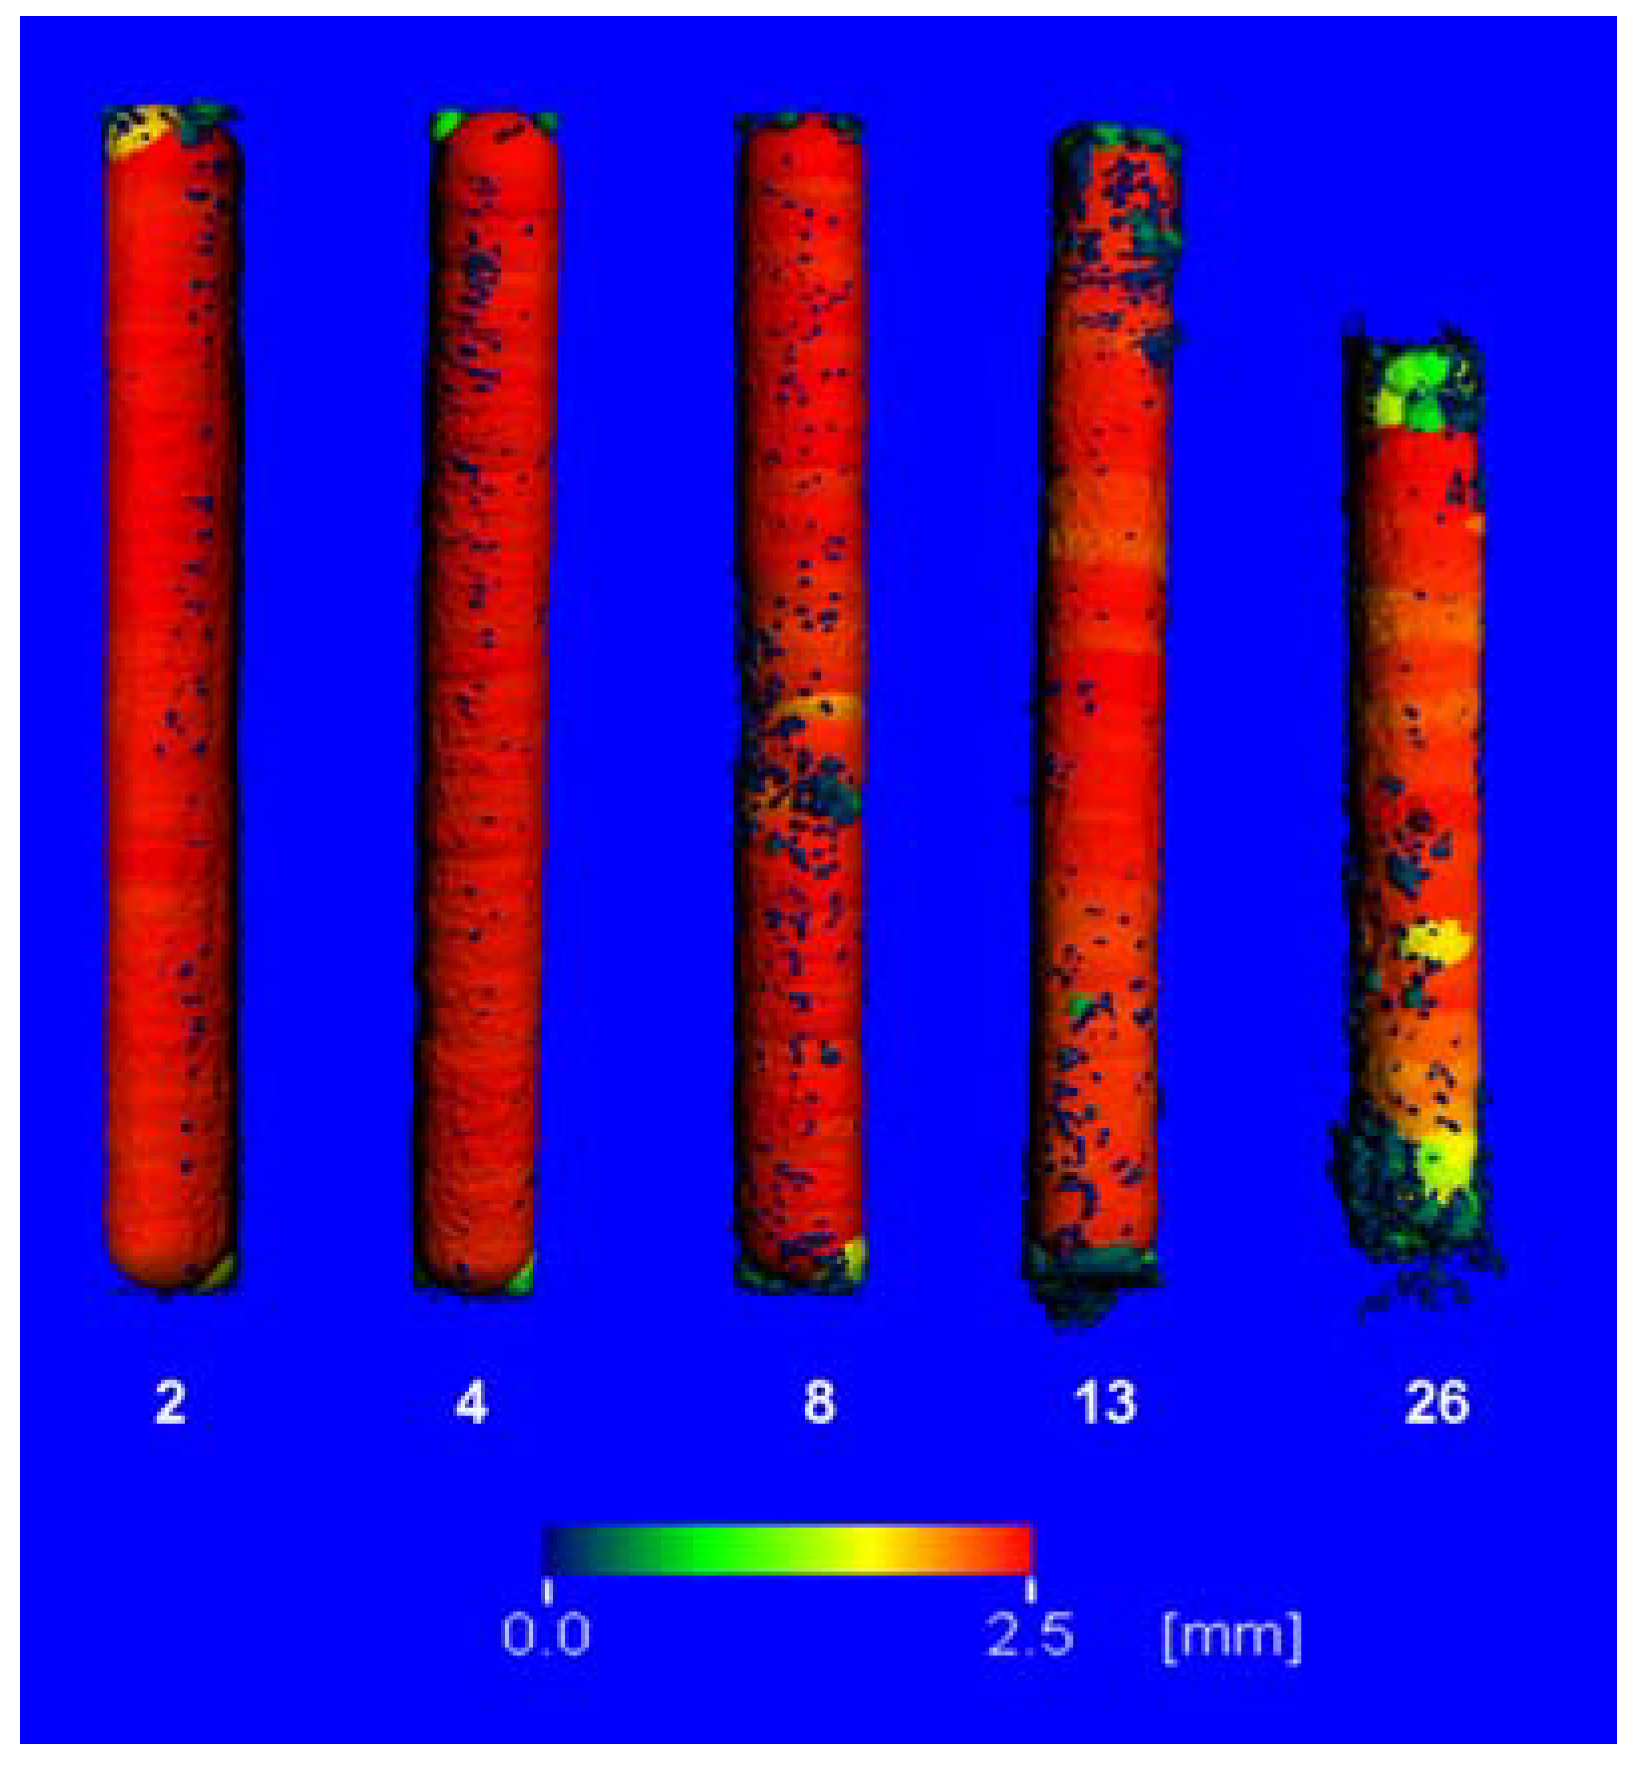

2.3. µ-Computed Tomographic Investigation of the in Vivo LANd442-Pins

3.2.5. In Vivo µ-Computed Tomography